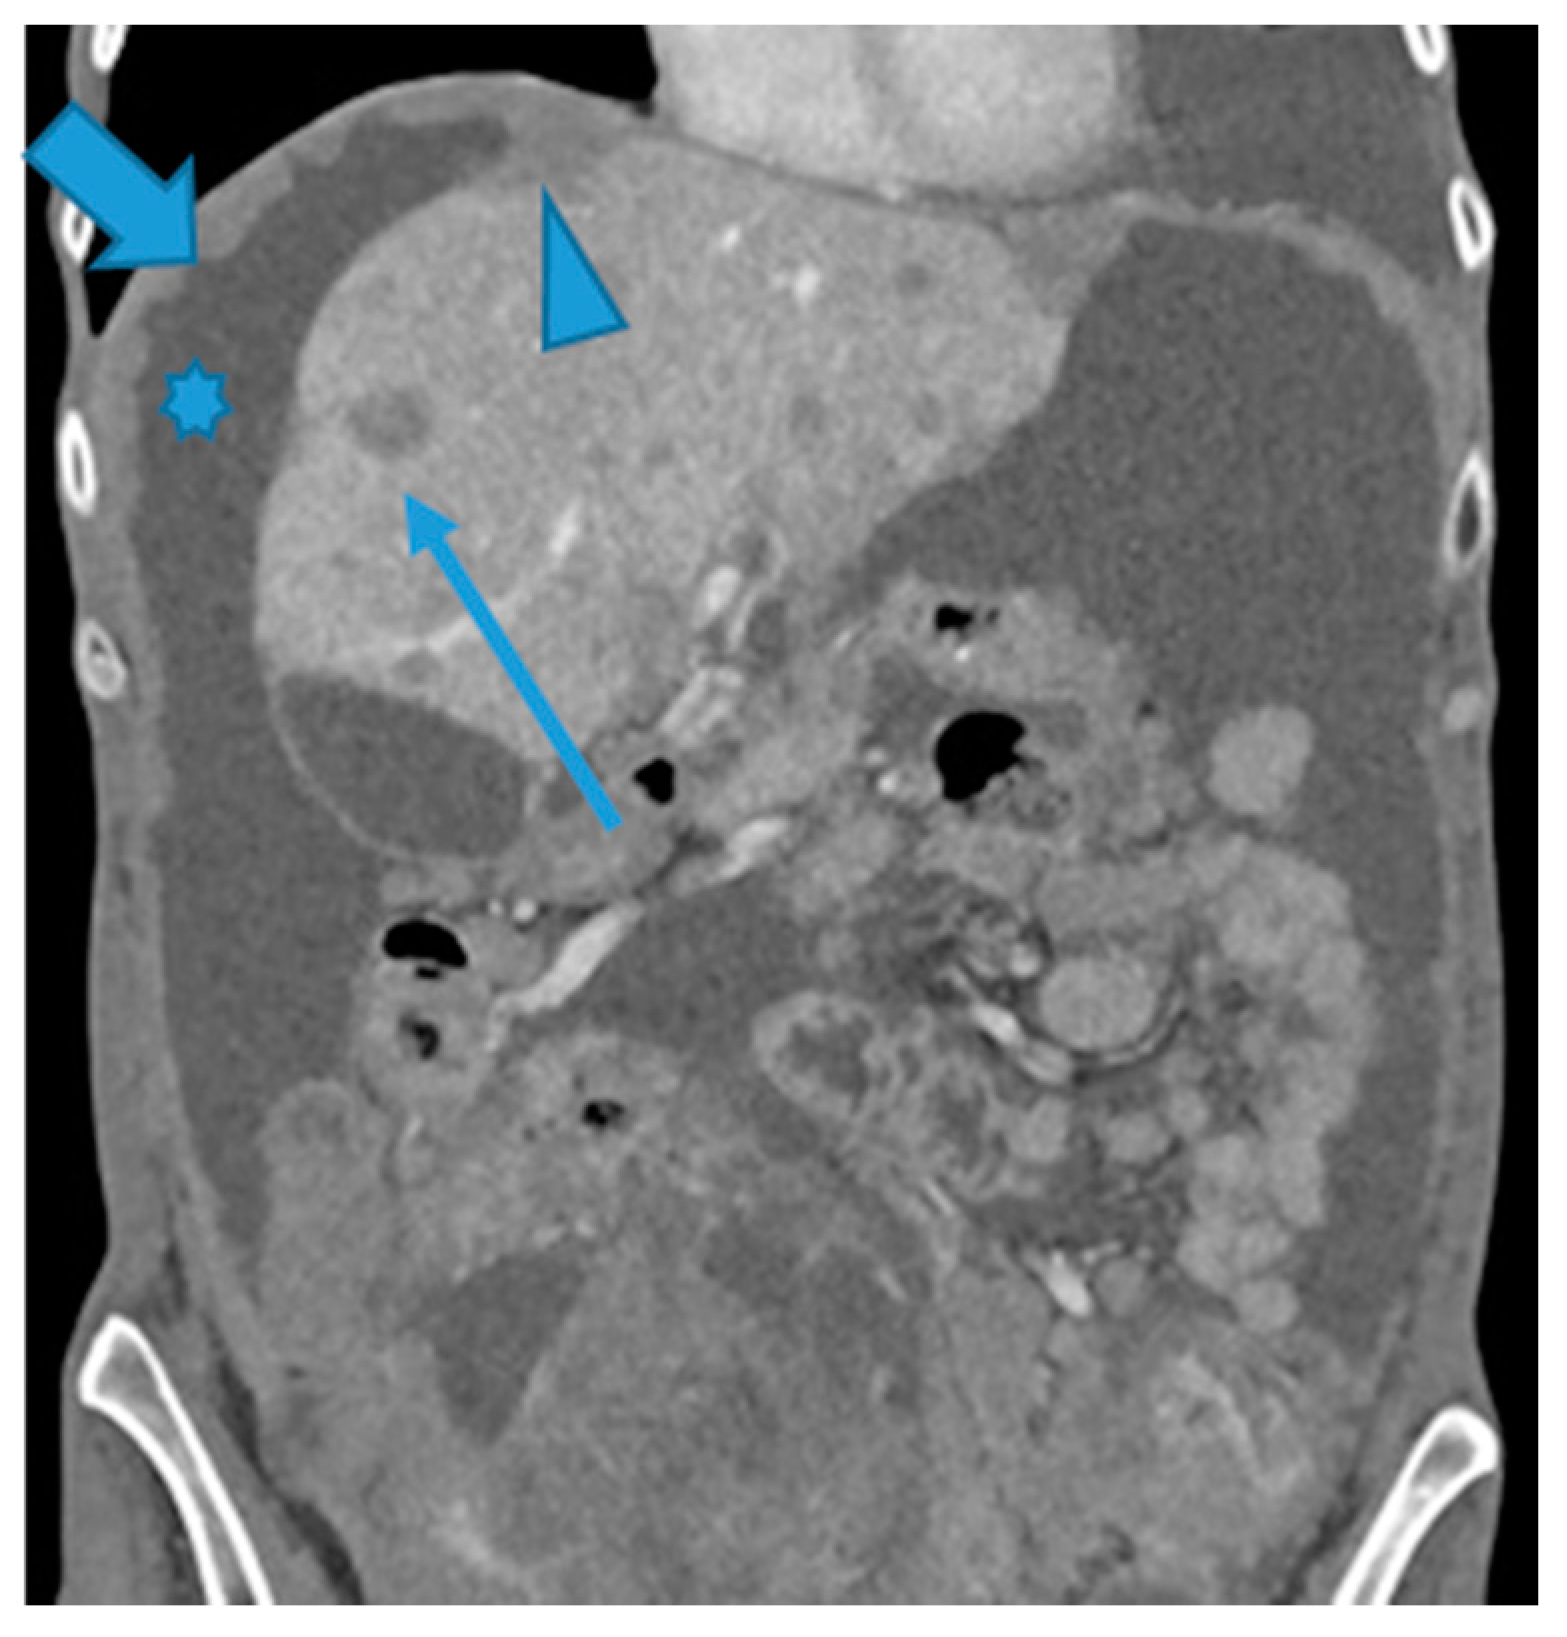

Figure 7.

CE-CT coronal MPR. PC from ovarian carcinoma: Multiple bilateral diaphragmatic nodular deposits (arrows). Notice how useful ascites (*) is to distinguish peritoneal deposits within the parietal peritoneum from deposits within the visceral (hepatic) peritoneum (arrowhead). Hepatic metastases (thin arrow).